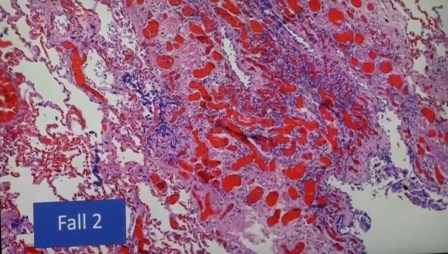

Aquí se ve el fenómeno que se llama la «pila de dinero»

Los grumos que forman los eritrocitos hasta que haya microtrombos. “No hemos visto microtrombos pero en sólo 10 pacientes es alarmante que se vea casos rarísimos como Sjörgen o Hashimoto”.